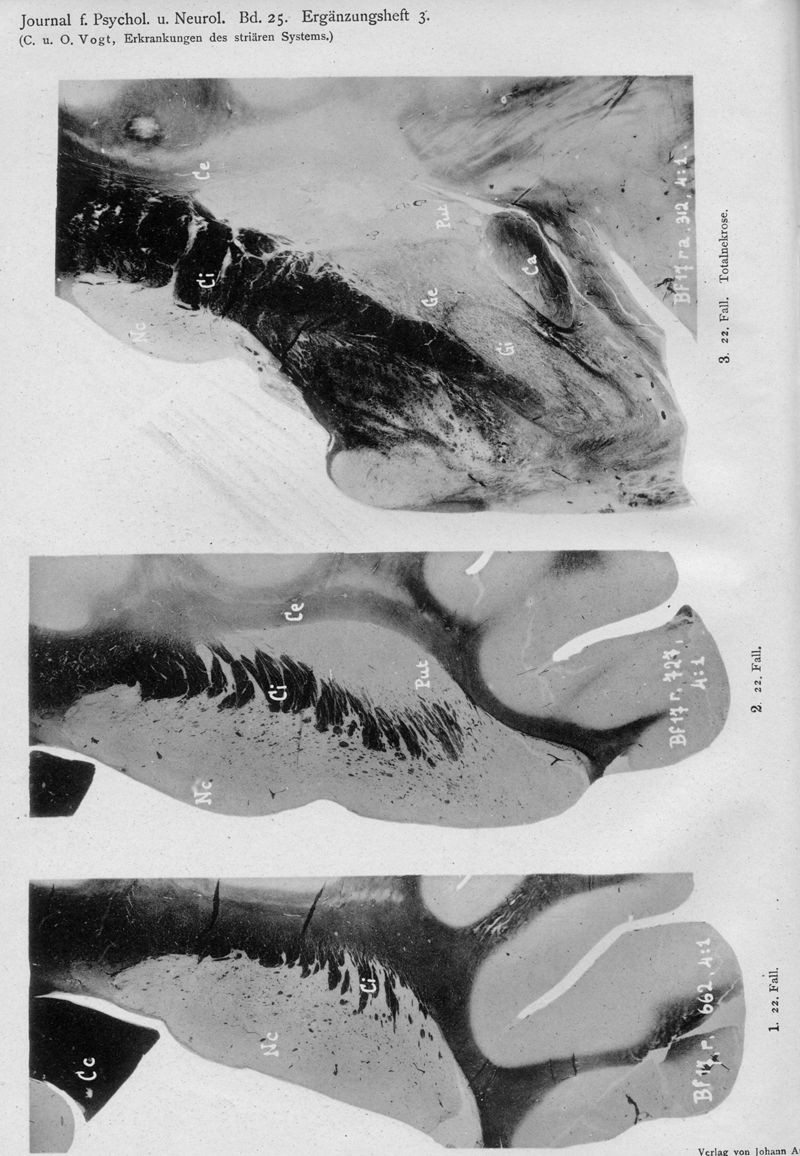

VOGT, Cécile / VOGT, O.

In : Journal für Psychologie und Neurologie,

1920, Vol. 25, pp. 627-846